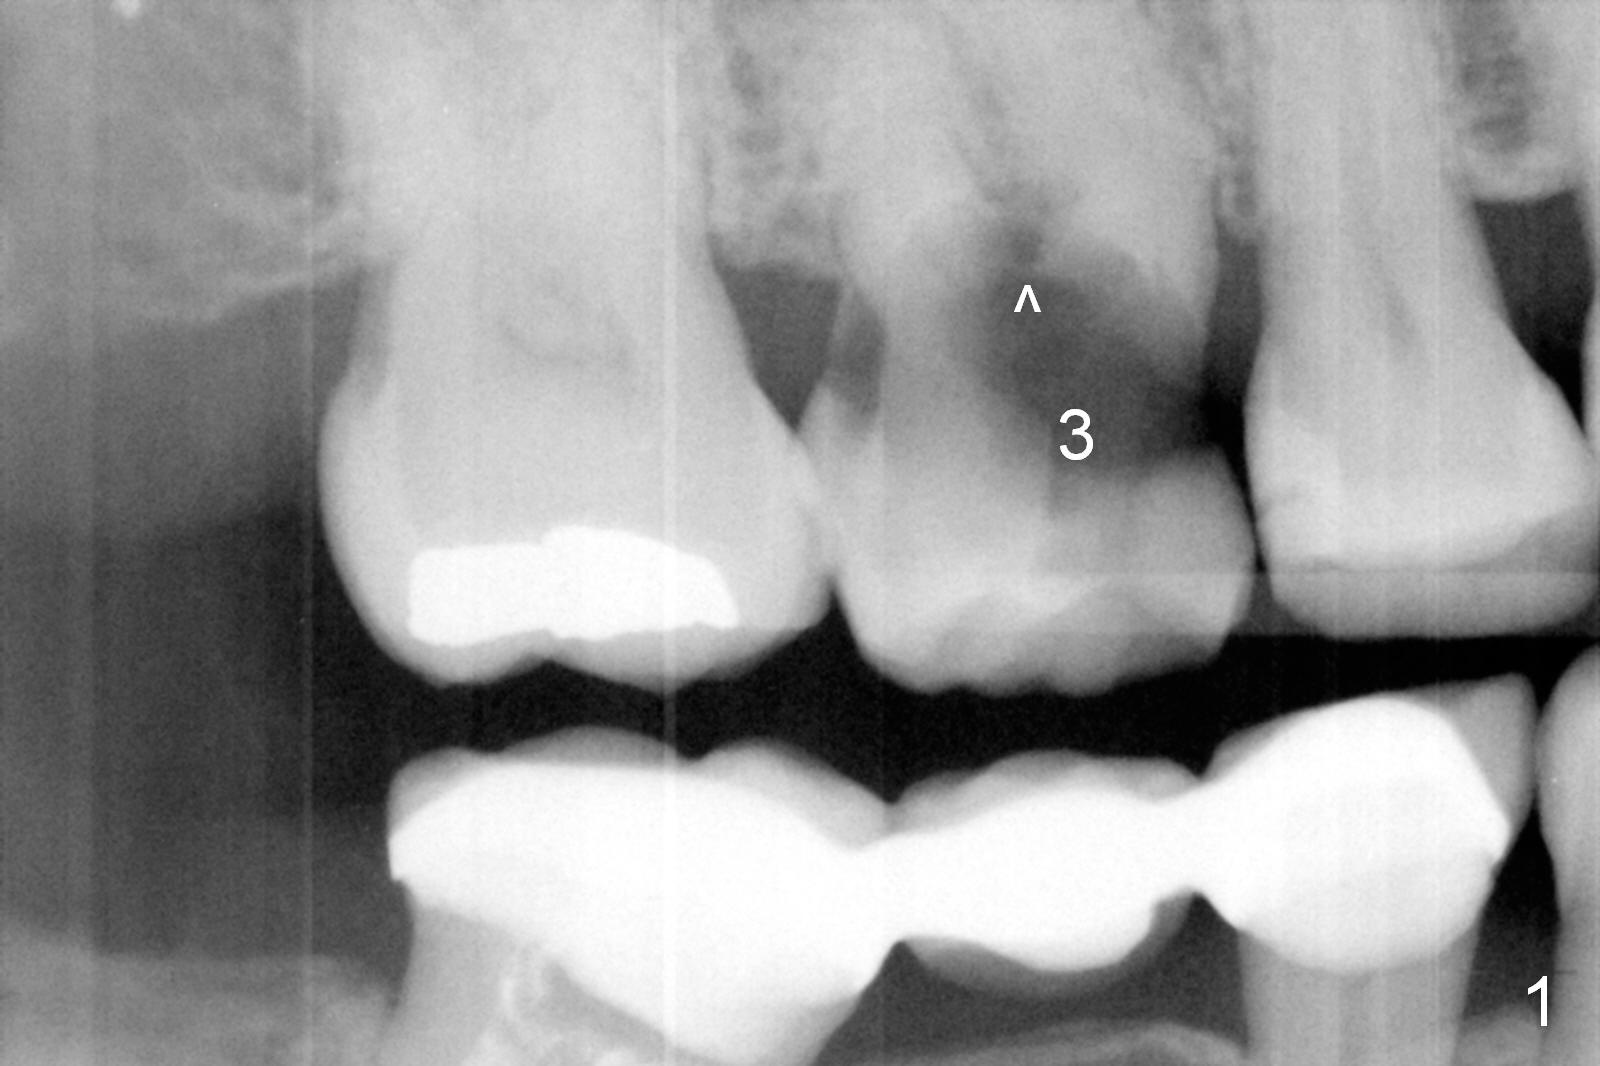

A 52-year-old woman is a dental phobic.  Her main concern is the tooth #3 with caries apparently involving the furca (Fig.1 ^).  Before extraction, take photos to show a polyp in the pulpal chamber, which is most likely periodontal.  After extraction (prepare surgical handpiece, since the tooth most likely fractures at extraction), take photos to show furcal perforation, while the socket is packed with 3 pieces of gauze soaked with Metronidazole.  There is apparently sufficient bone apical to the roots (Fig.2).  To achieve primary stability, use an implant as long as possible (13 mm of IBS, Fig.3 (implant is drawn to be placed too superficial)) with large diameter appropriate to the septum.  The plateau of the implant will be placed apical to the crests and coronal to the septum.